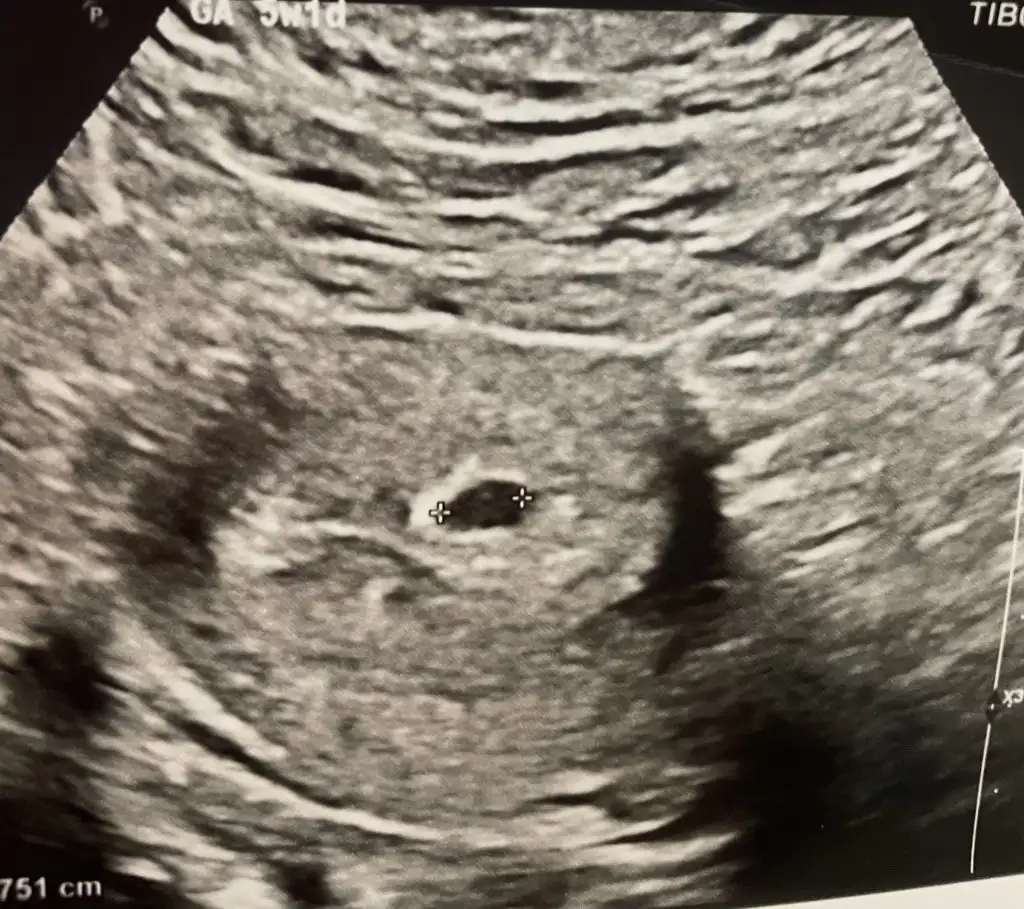

muhtemelen olabilir çünkü 6+2 olacağım

bugün ölçtürdüm 623 çıktı bende biliyordum aslında gözükmeyeceğimi ama bi ümit işte